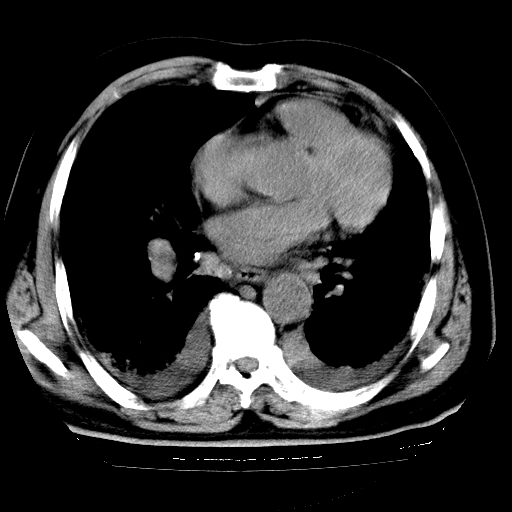

男,68岁,咳嗽、胸闷、发烧三天,查体:双肺散在湿罗音。

5.双侧胸腔少量积液;双侧胸膜增厚。

慢支合并感染.间质纤维化,心衰双侧少量胸腔积液

慢性支气管炎伴感染、肺气肿;间质性病变;双侧胸腔积液。